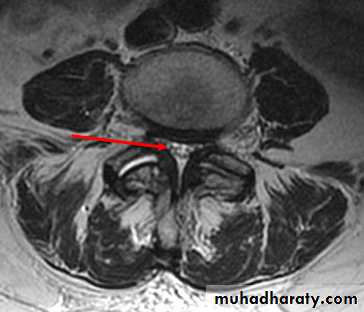

Tear in the annulus with herniation of the nucleus outside either laterally compressing nerve root, or centrally causing cauda equina or lumbar stenosis (neurogenic claudication)Lumbar Disc Syndrome

Central , sub articular, foramenal, extreme lateral